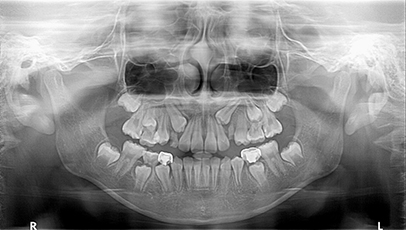

영구치 맹출이상 : 10세

영구치 맹출이상은 만 10세 전후로 많이 발생하고 주로 위턱 송곳니의 맹출이상이 대다수를 차지합니다. 한 치아의 맹출이상은 후속치아의 맹출에도 연쇄적으로 영향을 미치기 때문에 발견 즉시 맹출공간 확보를 위해 교정적으로 접근 하는 것이 매우 중요합니다.

영구치 맹출이상 성장교정

전후 사례

적절한 시기에 양쪽 위유치송곳니를 제거하였기 때문에 위송곳니가 제대로 내려오는 모습입니다